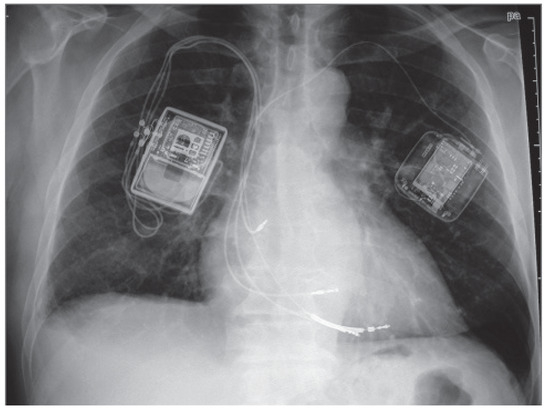

The device and implantation procedure

Cardiac contractility modulation signals are delivered by a device (the OPTIMIZER, Impulse Dynamics, Orangeburg, NY), the only clinically available system to date. The device resembles and is implanted like a large pacemaker in a minimally invasive procedure, but does not have pacing or anti-tachycardia therapy capabilities. The OPTIMIZER IV System, the last version of the device (the main change being a reduction in size from 58cc to 29cc, Figure 2A) was CE-marked and introduced in Germany in April 2013. It consists of a pulse generator implanted in the subclavian region with a rechargeable lithium battery that delivers CCM signals and three commercially available pacing leads that are introduced under fluoroscopic guidance as for a standard pacemaker (Figure 3). One electrode is positioned in the right atrium and is used only for sensing atrial activity to synchronise the system to apply the pulses exclusively during sinus rhythm. The ventricular electrodes, used for both sensing local electrical activity and for CCM signal delivery, are placed on the right ventricular septum at least 2cm apart. System implantation is guided by measuring acute increase in left ventricular dP/dtmax. If initial lead placement does not result in at least a 5% increase in dP/dtmax within approximately 10 minutes of signal application, the electrodes are repositioned. An external charger (Figure 2B) is used by patients to recharge the battery transcutaneously at home once per week, which usually takes about 90 minutes. Finally, a programmer (Figure 2C) is used to interrogate and program the device as for a pacemaker.

Figure 3. OPTIMIZER III system (implanted on the patient’s right side) with a single-chamber ICD (implanted on the patient’s left). Image reproduced with permission by Impulse Dynamics (Orangeburg, NY, USA).